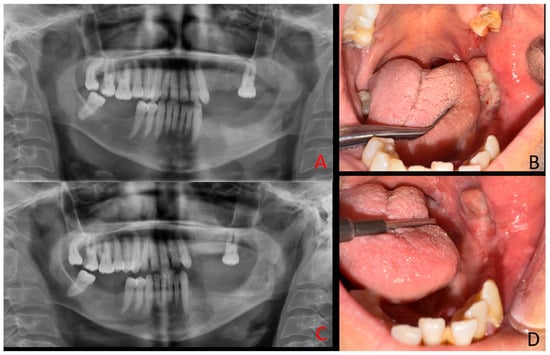

A 48-year-old female patient with a history of chronic renal failure on dialysis and regular use of anticoagulant and antihypertensive medications was referred for evaluation due to atypical mandibular pain, facial asymmetry, and swelling. Clinical examination revealed an irregular lesion in the left mandibular retromolar region with both intraosseous and exophytic components, accompanied by a foul odor suggestive of secondary infection. Typically, most cases of primary hyperparathyroidism (PHP) can be diagnosed relatively easily because of co-existing systemic morbidities, including bone symptoms (osteoporosis), urological signs (urolithiasis, polyuria, nocturia, hypercalciuria), gastrointestinal manifestations (loss of appetite, peptic ulcer), cardiovascular symptoms (hypertension, arrhythmia), neurological findings (muscle weakness), and psychological disturbances (headaches, depression, mood swings, sleep disorders). These features are mostly related to parathyroid over-secretion and subsequent calcium–phosphate–PTH imbalance. Since the patient was treated for a long time because of various general illnesses, with slowly progressive bone changes, the incidence of secondary hyperparathyroidism was suspected. Medical history revealed uncontrolled hypertension, chronic renal failure, and the patient undergoing dialysis three times per week. Heparin was administered on dialysis days, while aspirin was used on non-dialysis days. The patient also reported halitosis, which was confirmed during the clinical examination. Before surgery, the patient presented with swelling in the left facial region (A,B). Intraoral evaluation demonstrated that the pathological tissue was markedly fragile and prone to bleeding.